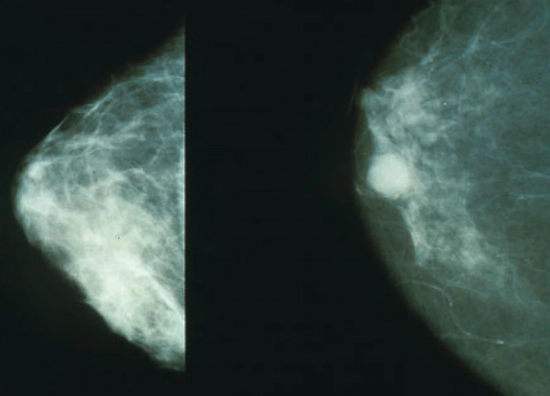

한편 남성 유방암의 원인은 정확하지 않지만 호르몬 이상, 가족력이나 유전적인 요인에 의한 것으로 추정한다. 유전적 유방암은 전체의 5~10% 정도다.

유방암과 관련된 유전자 BRCA 검사에서 돌연변이 양성으로 나온 경우 발병 확률이 증가한다. 혈연관계에서 2명 이상 유방암 환자가 있을 때도 유전성 유방암을 의심할 수 있다.

남성 유방암은 여성 유방암과 마찬가지로 수술, 방사선 치료 등으로 암을 제거한다. 재발했을 땐 조기에 발견하는 게 중요하기 때문에 일차 치료가 완료된 후에는 정기적인 추적 검사를 받아야 한다.